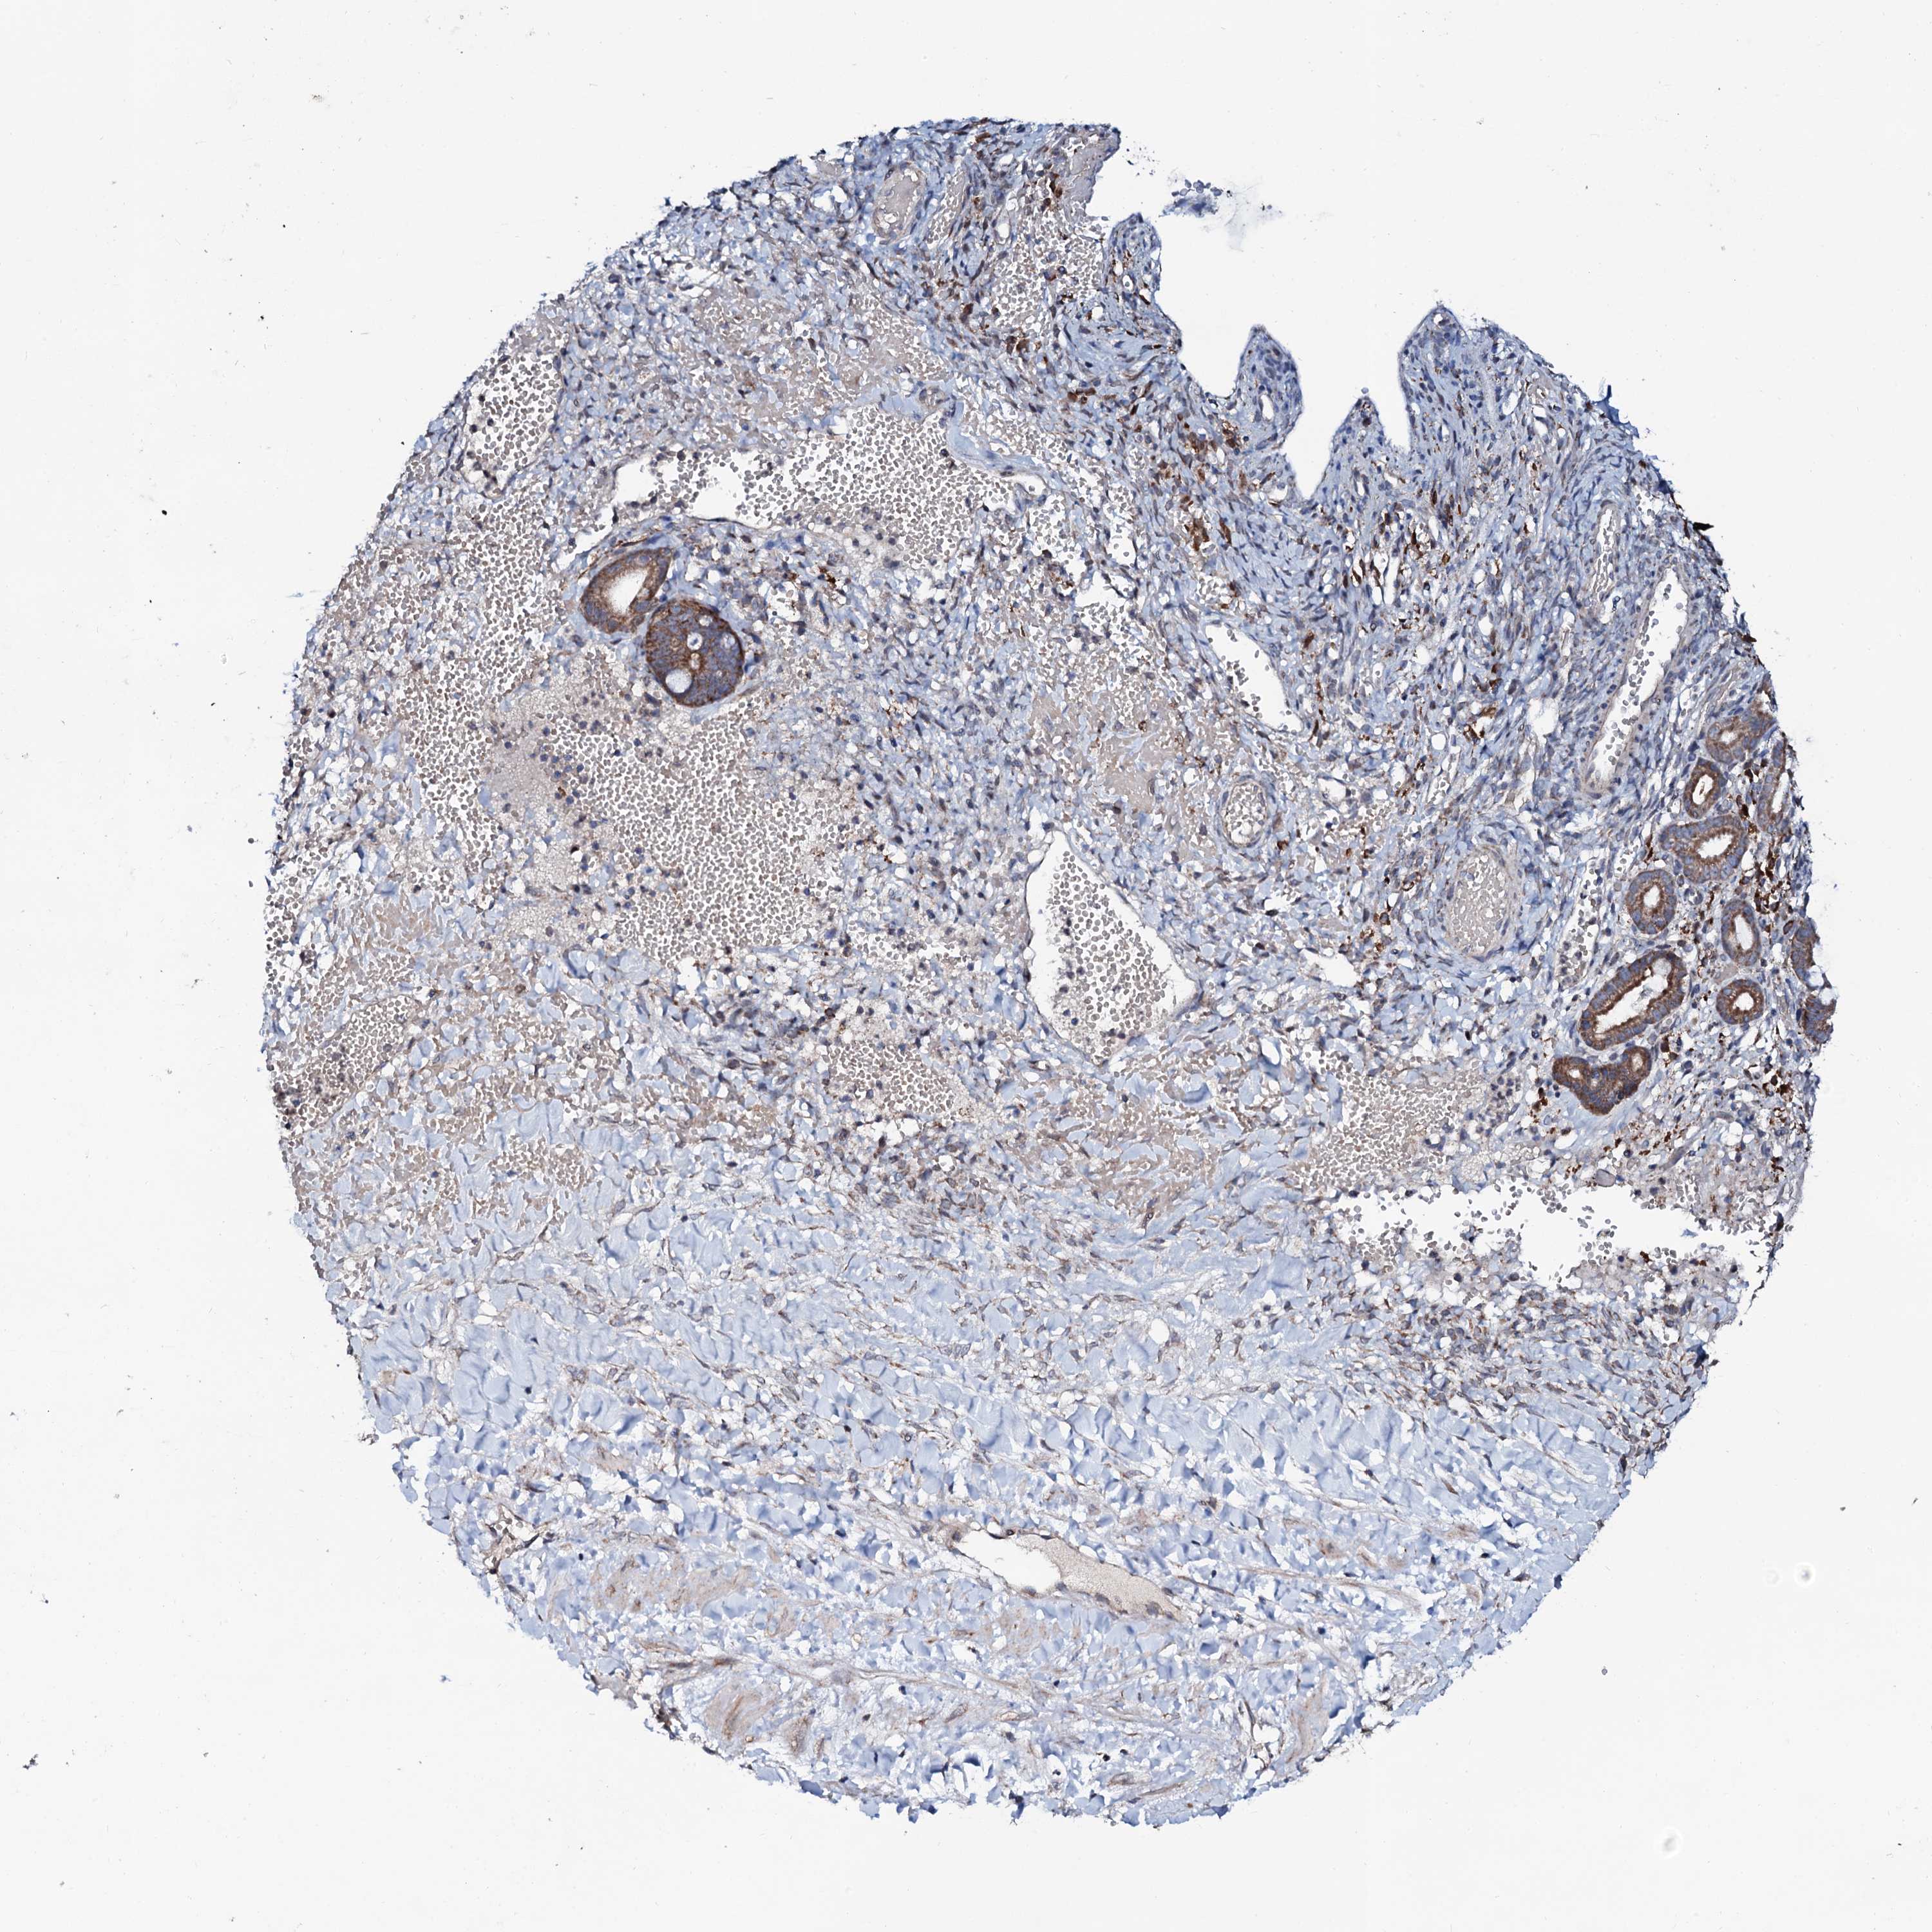

OVARIAN CANCER - Protein expressioni

A mouse-over function shows sample information and annotation data. Click on an image to view it in a full screen mode. Samples can be filtered based on level of antibody staining by selecting one or several of the following categories: high, medium, low and not detected. The assay and annotation is described here.

Note that samples used for immunohistochemistry by the Human Protein Atlas do not correspond to samples in the TCGA dataset.

Antibody stainingi

Antibody staining in the annotated cell types in the current human tissue is reported as not detected, low, medium, or high, based on conventional immunohistochemistry profiling in selected tissues. This score is based on the combination of the staining intensity and fraction of stained cells.

Each image is clickable and will lead to virtual microscopy that enables deeper exploration of all samples and also displays staining intensity scores, fraction scores and subcellular localization as well as patient and tissue information for each sample.

Antibody HPA041146

Cystadenocarcinoma, serous, NOS

Carcinoma, endometroid

Cystadenocarcinoma, mucinous, NOS

Carcinoma, NOS